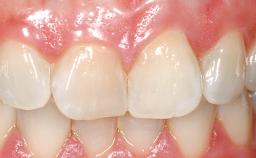

Immediate Flapless Placement of an Implant in a Maxillary Right Lateral Incisor Site

This 43-year-old male patient, a non-smoker, came to our practice because of a fracture of tooth 12 caused by a bicycle accident. Due to the combined para- and infrabony crown and root fracture, tooth extraction, and subsequent implant placement were suggested to the patient as the therapy of choice. The patient had high esthetic expectations with regard to the treatment outcome and asked for an immediate fixed provisional restoration. His individual esthetic risk profile summed up to a medium esthetic risk.

Patient's Esthetic Expectations Low Medium High

Esthetic Risk Medium